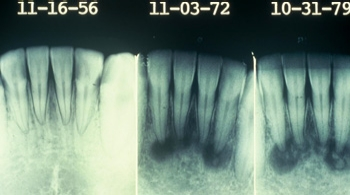

Figure 2 : Dysplasie périapicale cémento-osseuse progressive sur une période de 23 ans. Jacoway J. Tiré de » General and Oral Pathology for the Dental Hygienist « , Lippincott, Williams & Wilkins, Baltimore 2008. Chapitre 20.

Souvent, la dysplasie cémento-osseuse périapicale peut être suivie lorsque le patient est vu périodiquement sur une longue période. La deuxième image présentée ici s’est produite sur une période de 23 ans avec observation (voir figure 2).